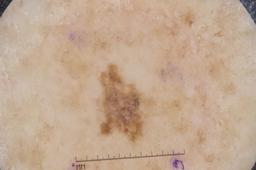

MSK-4

- Name: MSK-4

Description:

Images found based on a search for patients with a personal history, clinical diagnosis, or differential diagnosis of melanoma. All diagnoses confirmed by histopathology.